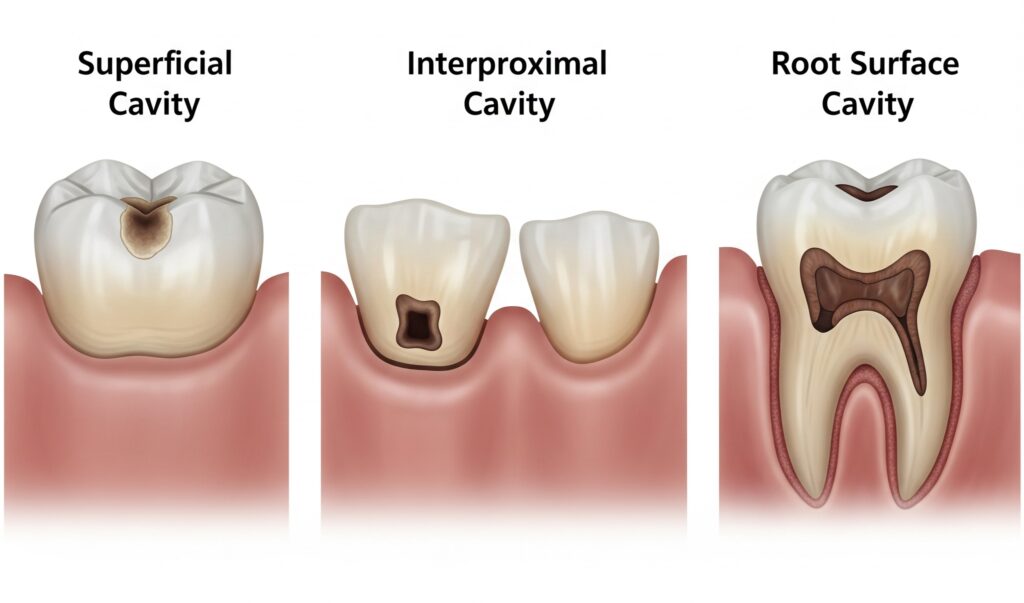

Non tutte le carie sono uguali. Durante la mia esperienza come dentista a Trento, ho potuto classificare le diverse tipologie di carie in base alla loro localizzazione, profondità e velocità di progressione.

La carie superficiale rappresenta la forma più comune e fortunatamente più facilmente trattabile. Questa tipologia interessa esclusivamente lo smalto dentale e spesso si presenta come una piccola macchia bianca opaca o brunastra sulla superficie del dente. La carie superficiale è spesso asintomatica e può essere individuata solo durante controlli periodici presso il nostro studio dentistico.

Le carie interprossimali si sviluppano negli spazi tra i denti, dove l’accumulo di placca è favorito dalla difficoltà di pulizia. Queste carie sono particolarmente insidiose perché rimangono nascoste alla vista diretta e possono progredire significativamente prima di essere scoperte. Nel nostro studio utilizziamo radiografie bite-wing digitali ad alta definizione per individuare anche le carie interprossimali nelle fasi iniziali.

Le carie della superficie radicolare colpiscono principalmente i pazienti più anziani, dove la recessione gengivale espone la radice del dente. Questa superficie, non protetta dallo smalto ma solo dal cemento radicolare, è particolarmente vulnerabile all’attacco batterico e richiede un approccio terapeutico specifico.